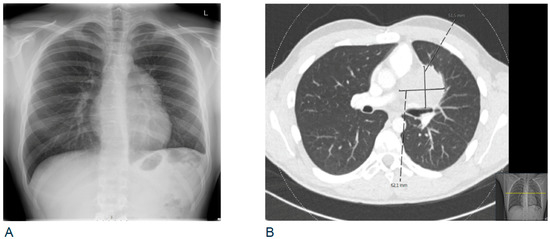

2.1. Clinical Description and Histological Findings